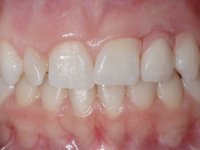

Female patient, 24 years of age, non-smoker. The clinical situation resulted from an orthodontic treatment performed with the intention of resolving a problem of unilateral agenesis of the left lateral incisor. After orthodontic correction, an implant was placed at the site of tooth 2.2. During the period of osseointegration the patient used a removable orthodontic appliance with a prosthetic tooth. Upon assessment of the situation, I registered the following aesthetic conditions:

1. The cervical level of the teeth 1.3.1.2 and 1.1 are at a more incisal level than the teeth 2.1 and 2.3.

2. The distal papillae of 2.1 and mesial of 2.3 disappeared.

3. Slight radicular exposure in distal 2.1 and mesial 2.3.

4. The edentulous space corresponding to the high and narrow 2.2.

5. Tooth 1.2 with microdontia and rolled.

An impression was made on the implant with open tray technique using soft and regular consistency putty. At the laboratory, after confection of the work model, a diagnostic waxing was performed, which sought to find an aesthetic compromise solution. In this sense, a temporary workpiece screwed onto the implant was used to simulate the difficulties we would have with screwing the definitive work. This study abutment consisted of wax to reproduce soft and hard tissues, seeking to anticipate the use of ceramics of gingival and coronary shade. Also, part of the interproximal papillae corresponding to the distal portion of the 2.1 tooth and the mesial tooth of the tooth 2.3 were also waxed, anticipating the use of composite resin “chips” with gingival tonality. Finally, a veneer was waxed to correct the microdontia of the tooth 1.2. In this waxing, the vestibular emergence of the orifice for access to the screw of the implant abutment was evident. Once this therapeutic option was accepted, the implant abutment in polymerized composite resin was prepared at the lab, as well as the papillary "chips", also in composite resin of gingival tonality. Tested in the mouth, the abutment was screwed and the "chips" bonded. The access hole of the screw was filled with composite resin. In subsequent consultation, a gingivectomy was performed on the cervical contour of teeth 1.3, 1.2 and 1.1 with the aim of correcting the asymmetry between the first and second quadrant. After the soft tissues were cicatrized, a dental bleaching was performed according to the patient’s aesthetic requirements. Final impression on the implant was made using the silicone open tray technique, taking care to individualize the transfer piece by copying the emergence profile of the patient’s provisional abutment. At the laboratory, the impression yielded a definitive working model, on which the abutment was waxed on a plastic insert. This process was carried out with the orientation of a wall of silicone based on diagnostic waxing. The wax made on the plastic part was placed in a special holder that allowed its scanning in a laboratory scanner. This scan by CAD process informed the design of an abutment in Zr. later materialized by a CAM process. The Zr. abutment was tested in the mouth, validating its clinical and imaging establishment. During this consultation, the choice of color was made by the ceramist, of both the coronary ceramics and the ceramic of gingival tonality to be used. Individualized color scales were used. At the laboratory, the coronary and gingival ceramics were placed on the implant abutment and later, on a working model with refractory gypsum, a veneer of feldspathic ceramic was made. This veneer was built on a surface specially designed for this purpose in the abutment. This surface tried to reproduce a dental preparation performed for the same effect. In the mouth the abutment was screwed with a torque of 35N, the access hole to the screw was filled with Teflon and later filled with composite resin. The veneer was bonded onto the implant abutment using the conventional bonding technique, with relative insulation. For economic reasons, the patient did not proceed to perform the veneer on tooth 1.2. Although a limited aesthetic compromise was expected from the outset, a result was achieved which satisfied the patient.